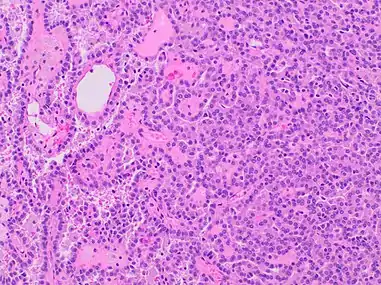

| Papillary renal cell carcinoma, type 1, characterised by tubulopapillary architecture with admixed foamy histiocytes in the papillary cores. | |

Type 1 PRCC, also known as a renal tumor caused by a genetic predisposition of hereditary papillary renal cancer syndrome, compromises approximately 25% of all PRCCs.[14][15] In the perspective of immunochemistry, it has a profile of strong CK7 and alpha-methyl acyl-CoA racemase (AMACR) expression at most focal CA-IX expression.[16] Histologically, its epithelium is composed of relatively small-sized simple cuboidal cells lined in a single layer.[17] These cells are well-characterized by basophilic cytoplasm.[18] Due to its solid growth, an extremely compact papillary architecture is often observed.[16] Other morphological characteristics include intracellular hemosiderin and foamy macrophages placed inside of papillary fibrovascular cores or psammoma bodies.[19] In general, the nuclei of type 1 PRCC belong to grade 1-2 of the Fuhrman system.[16]

A micrograph of type 1 PRCC, illustrating features of small basophilic cells with scarce cytoplasm. A single layer of cells are surrounding the basal membrane.[20] Foamy macrophages are inside of papillary fibrovascular cores.

Type 1 PRCC, this case being more compact at right.